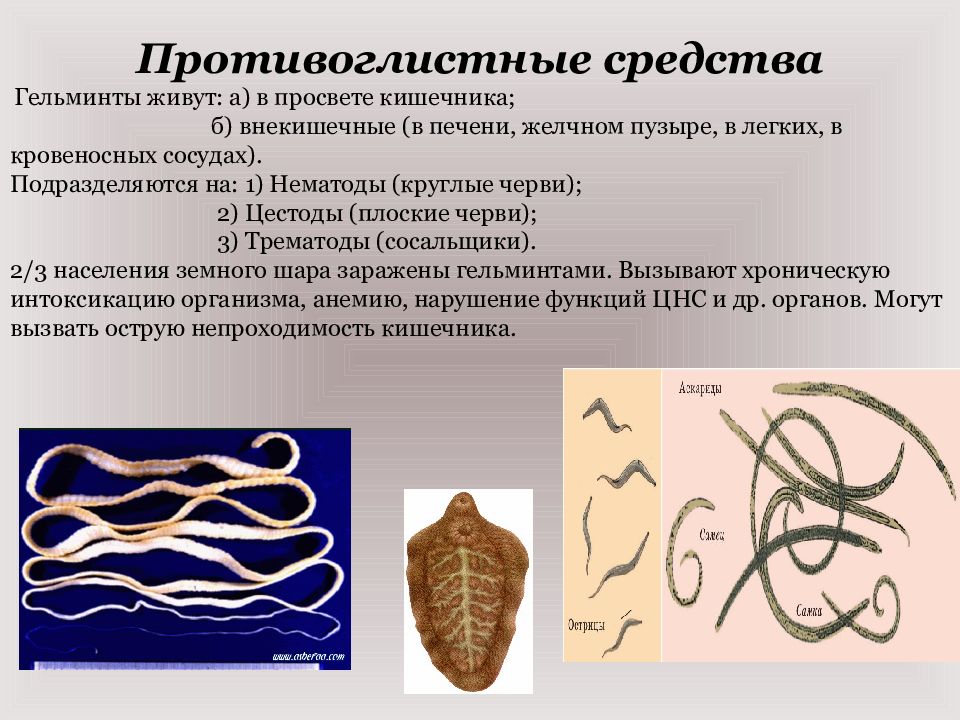

Фотографии нематод, цестод и трематод в природе

Раздел: Другие животные